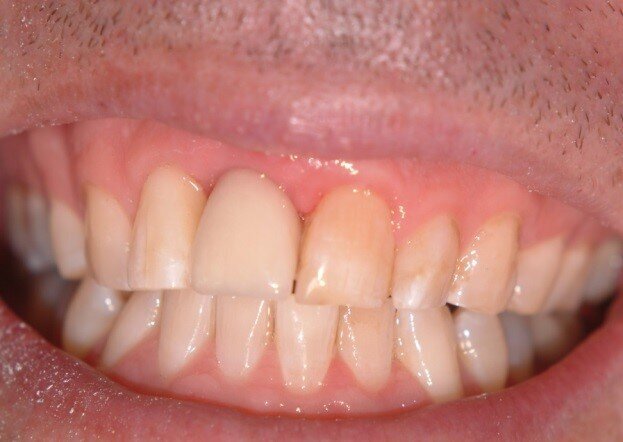

Patient RR was a healthy non-smoking 44 year old male who presented with a complaint of an unaesthetic upper right central incisor with extensive recession showing a large amount of darkened labial root surface. The situation was worsened by a high smile line and a porcelain crown contrasting dramatically with the root colour. He had had periodic swelling at the apical part of the recession over a long period. There was a history of trauma in his teens leading to root canal treatment and a crown, and subsequent apicectomy in his 20s. Clinical examination revealed an otherwise periodontally healthy, well looked-after mouth. (Fig. 1, 2, 3)

Diagnosis was of endodontic failure and possible root fracture leading to loss of labial bone and soft tissue.